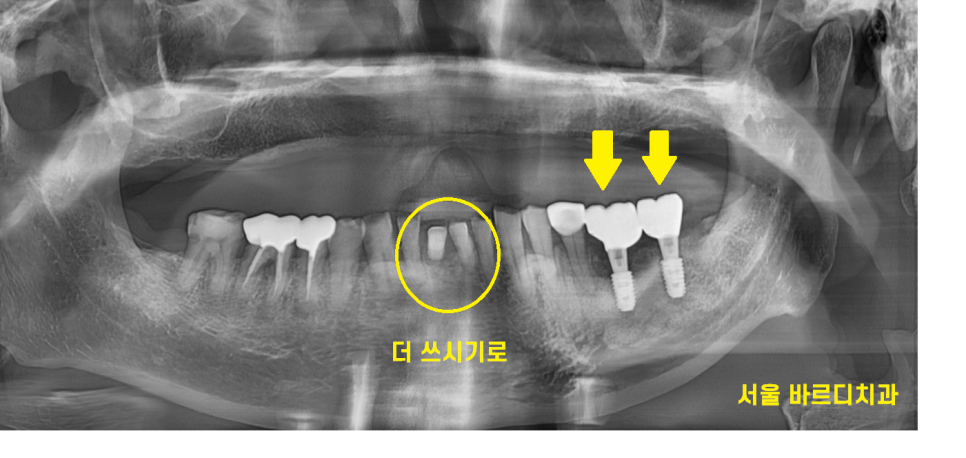

23.11.14

80대 임플란트

완성 후 사진입니다.

앞니도 문제가 있긴 하였는데

잘 씹히는 게 중요하다고

더 쓰신다 하셨어요.